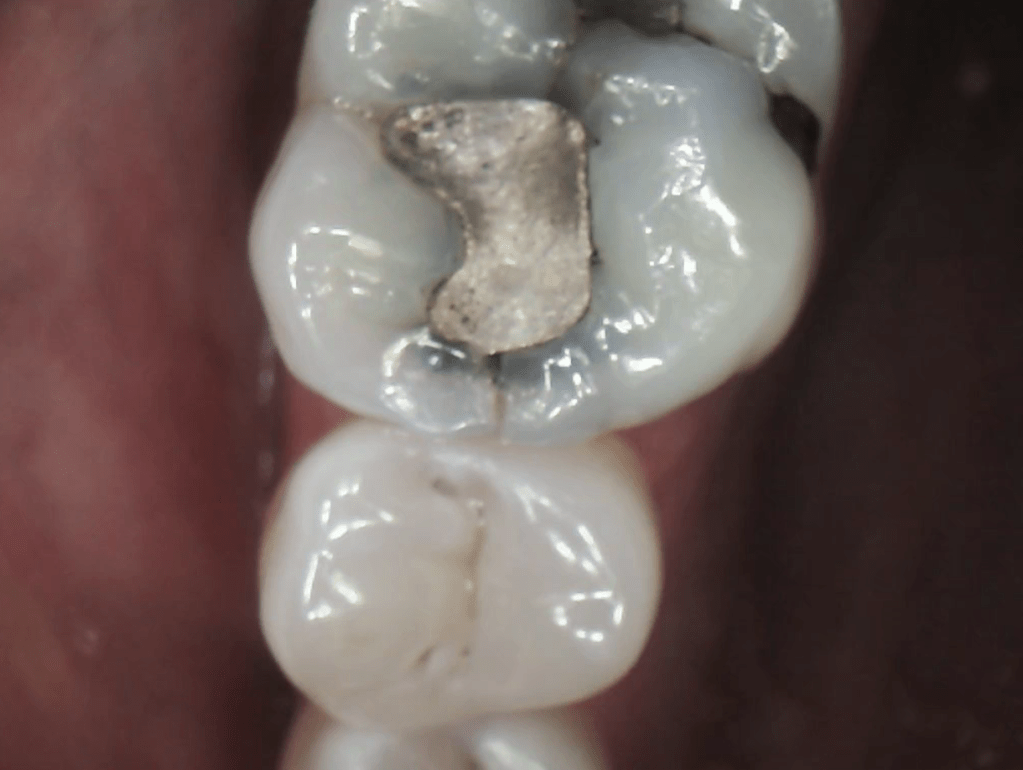

Fractured Tooth and Broken Metal Filling